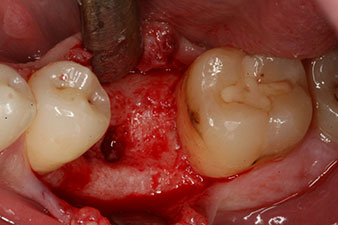

Шест седмици след екстракцията се открива непълна осификация след препарацията на мукопериосталното ламбо в областта на предходната алвеола мезиално.

Имплантът е поставен както е планирано след цялостно отстраняване на гранулационната тъкан (blueSky, bredent).